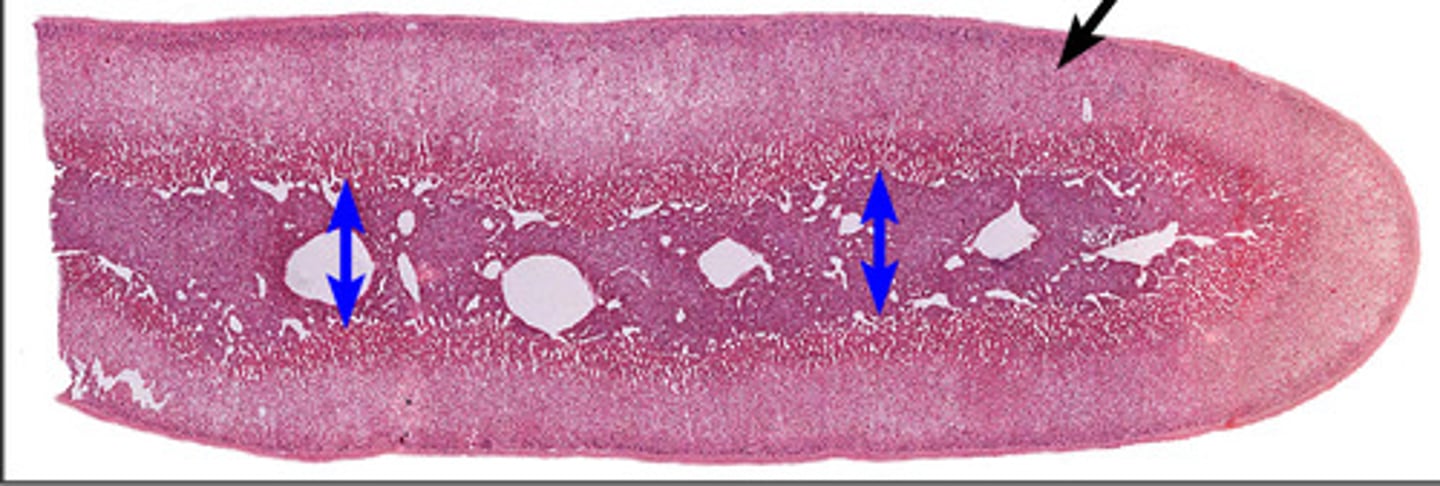

Gray matter

Posterior horn

Anterior horn

Lateral horn

G

Gray commissure

gray matter around this structure

Central canal

White matter

Posterior funiculus

Green

Anterior funiculus

Yellow

Lateral funiculus

Red

Posterior median sulcus

green

Anterior median fissure

red